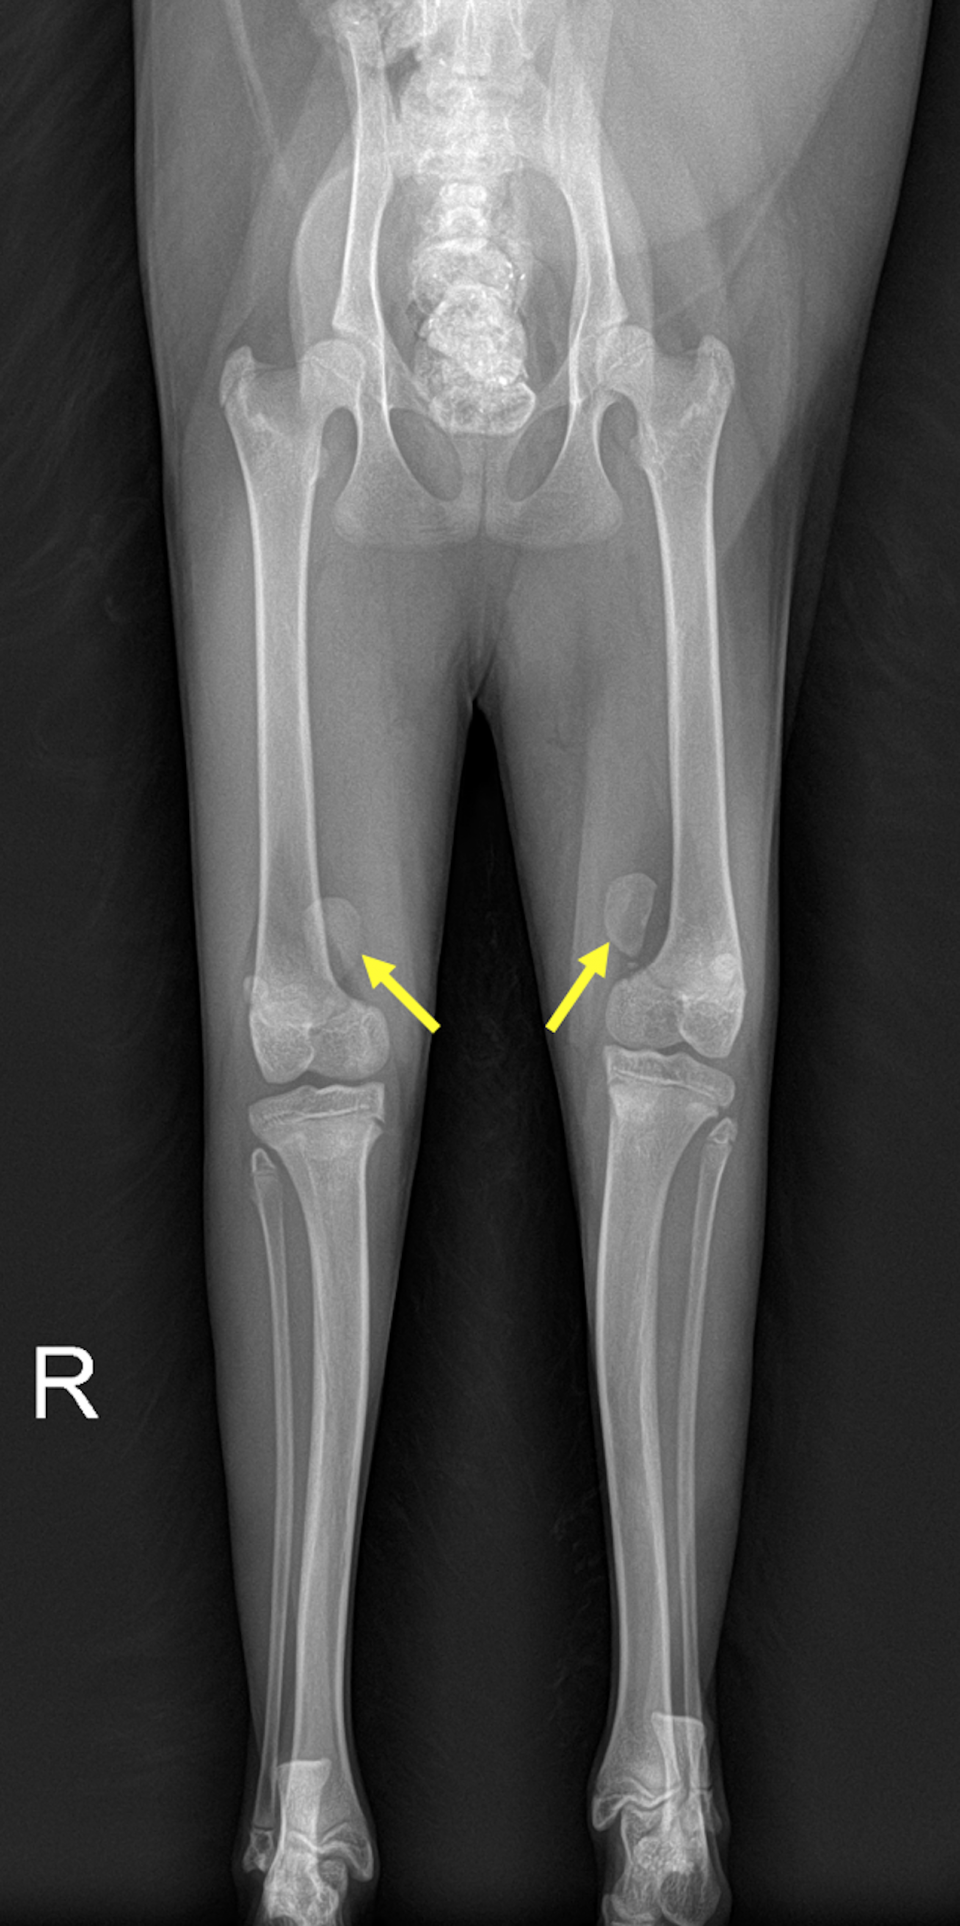

左グレード4、右グレード3の膝蓋骨内方脱臼が認められました。

グレード4で常に脱臼している左後肢は、膝を伸展させられず足が内側に捻れ、負重していませんでした。